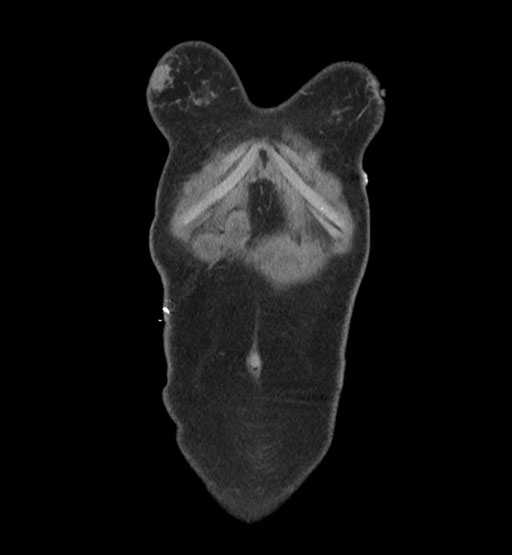

Imaging Analysis

Look through the patient's CT scan to identify any areas of concern for the necessary procedure.

Based on initial findings, which issue(s) would you be most concerned about?